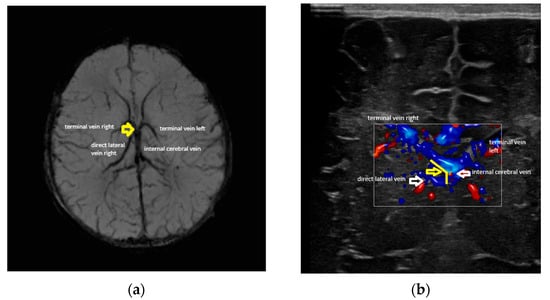

- Confluence at the level of the foramen of Monro (Figure 2).